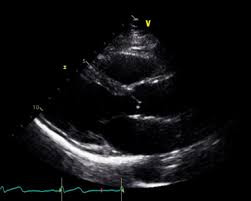

심장 초음파란 어떤 검사인가?

심장 초음파는 초음파를 이용해 심장의 크기, 움직임, 판막 상태, 혈액 흐름을 실시간으로 관찰하는 검사입니다. 방사선 노출이 없고 통증도 거의 없어 반복 검사에도 부담이 없습니다. 특히 심장 질환이 의심될 때 가장 기본적으로 시행되는 검사로, 심장 초음파로 알 수 있는 병의 범위는 생각보다 매우 넓습니다.